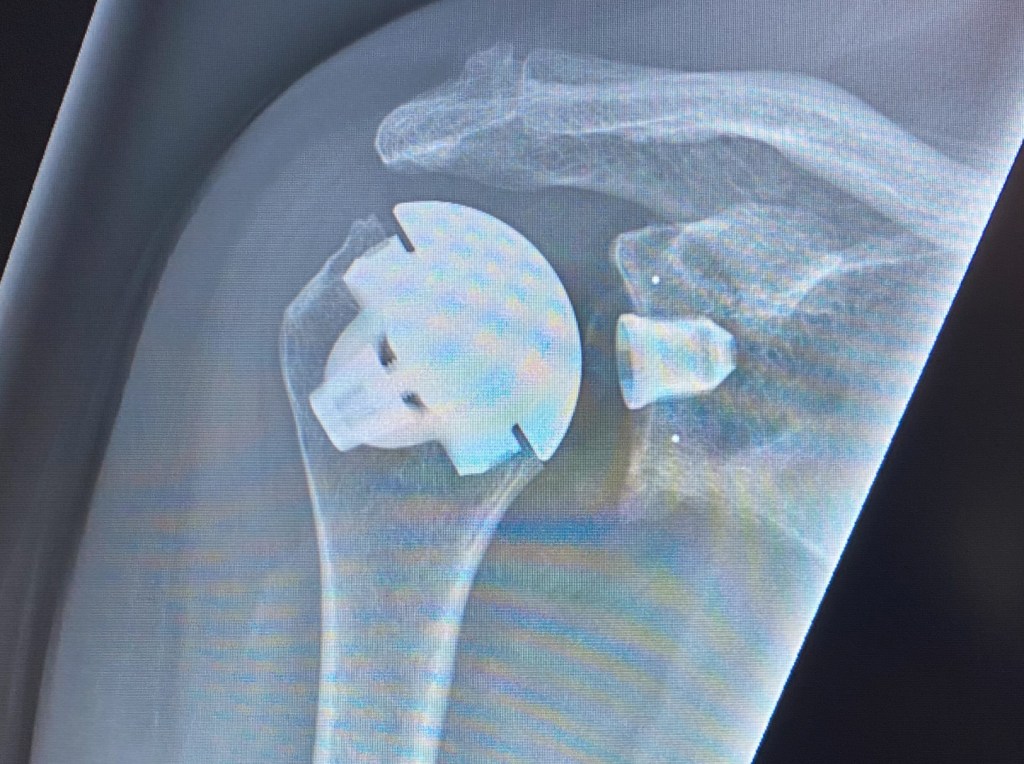

Gode Gud ge mig tålamod – men gör det fort!

Rubriken är titeln på den eminente Lasse Erikssons bok från 2005, men lite så jag känner just nu. Idag är det precis två veckor sedan jag gick in på Capio Movement i Halmstad och på eftermiddagen vaknade upp med en ny axelled. Vad har vi pysslat med sedan dess då?…

Att börja på ny kula…

Uttrycket ”Att börja på ny kula…” är väl allmänt vedertaget och nu känns det som om jag helt bokstavligen gjort just det… I onsdags skulle jag vara på Capio Movements i Halmstad klockan 09 så morgonen började för min del med vatten, kaffe och äpplejuice, medan Lars försåg sig med…